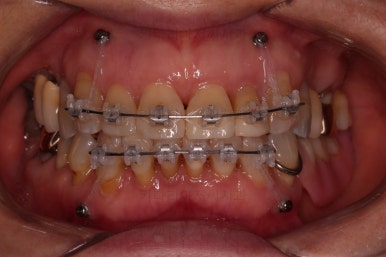

우선 장치를 부착하고요.

가지런하게 하면서 치간삭제 및 기존 떼워진 수복물을 제거한 뒤에 틈을 만들거나 모아줘요.

잇몸에서 주욱 빠져나와서 길어보이던 치아를 다시 잇몸 속으로 원위치 시키는 작업을 같이 해줘요.

점점 부산부분교정을 통해 가지런해지면서 틈새가 모이는 걸 볼 수 있어요.

치아가 없는 부분은 틀니도 병행해서 사용하셨고요.